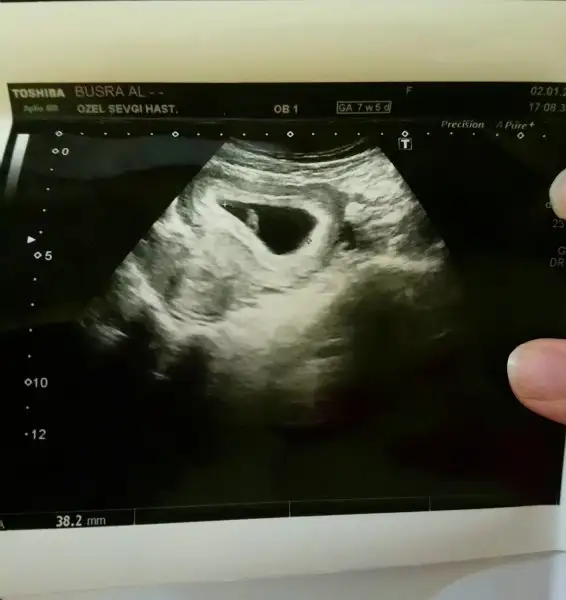

Mrba Kizlar üzücü haberleri okudun.Allah sabir versin inşallah sağ salim tekrardan bebis haberi alırsınız..bu arada bende bugün bi kaç Dr.un kalp atışı yok kese de bebek yok demelerinden sonra çok strese girip özel hastaneye gittim..Dr baktı kese var bebek var kalp atışı yok dedi gebeliği sonlandırmak için radyoloji raporu gerekli radyolojiden sıra alıp detaylı baktirmami istedi.gittim en son sıra benimdi 2 saat nasil geçti anlatamam öldüm öldüm dirildim resmen ama çok şükür ki radyoloji uzmanı bebegimin kalp atışlarını dinletti gösterdi gayet sağlıklı dedi ağladım o an çok şükür Rabbine normalde SATA göre 7+5 olması gerekirken 7+1 uyumlu çıktı

bu arada tahminci anneler bana da bi el atin bende tahmin istiyorum karından bakıldı ultrason

Eklentiler

• _20180103_034256.webp

_20180103_034256.webp

12,2 KB · Görüntüleme: 83